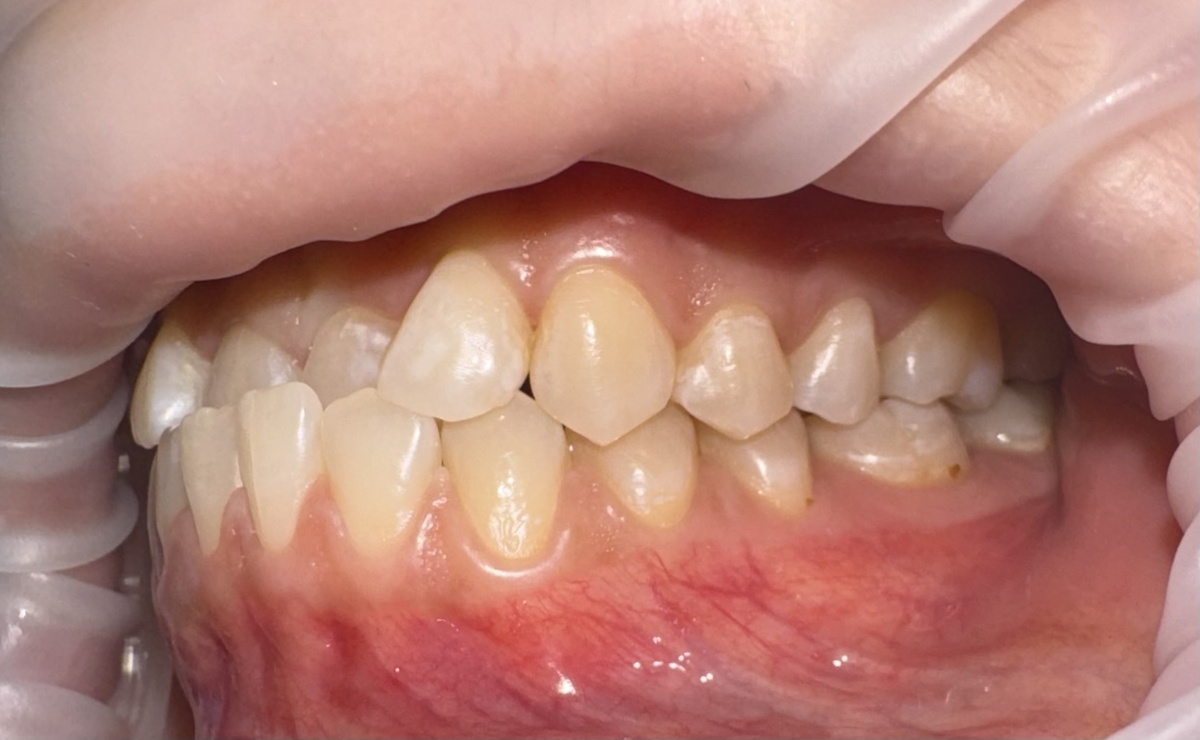

К нашему ортодонту Ксении Владимировне Снитковой пришла пациентка с довольно сложным прикусом:

Сужение верхней челюсти, сужение нижней. И обратно-резцовое перекрытие - это когда нижние резцы стоят впереди верхних и, при каждом смыкании, работают как наждачка. Режущие края верхних зубов сильно стёрты:

И это не от возраста, не от бруксизма, а просто потому, что им некуда было деться от этой ежедневной мясорубки...

«У пациентки сужение верхней челюсти, сужение нижней челюсти, обратно-резцовое перекрытие - нижние резцы перекрывают верхние. Поэтому на фото видна очень большая истираемость по режущему краю верхних резцов. Мы расширили боковые сегменты сверху и снизу, поставили большие разобщающие накладки. Даже во фронте у неё они были с активной плоскостью, чтобы дать правильный торк резцам. Потом накладки убрали, сомкнули зубы. Пациентка носила тяги, потому что нижняя челюсть склонна к выдвижению вперёд. И вот - такие хорошие результаты уже через год».